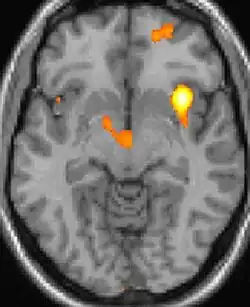

| Diese PET des Gehirns überlagert mit einer Kernspintomographie zeigt eine erhöhte Aktivität in der Schmerzmatrix und im Hypothalamus rechts | ||

Die Positronen-Emissions-Tomographie (PET)-Darstellungen oben zeigen die funktionellen Daten, also die Bereiche, welche bei Schmerzen Aktivität aufweisen, im Vergleich zum Aussehen bei einem schmerzfreien Intervall. Man sieht die sog. Schmerzmatrix, die immer bei Schmerz aktiviert ist und das Areal in der Mitte (in allen drei Ebenen), welches spezifisch im Cluster-Kopfschmerz aktiviert ist. Die VBM Bilder unten zeigen die strukturellen Daten. Hier wird untersucht, ob die Gehirne von Cluster-Kopfschmerz-Patienten anders sind als die Gehirne von Menschen ohne Kopfschmerzen. Nur ein Areal ist anders, da es mehr Graue Substanz enthält: Dieses entspricht dem oben gezeigten funktionellen Areal. Es handelt sich um den Hypothalamus. Dort wird unter anderem der Schlaf-Wach-Rhythmus generiert. Man vermutet daher den Motor des Cluster-Kopfschmerzes im Hypothalamus.[27][28] Mit der 1H-Magnetresonanzspektroskopie konnten auch biochemische Unterschiede zwischen dem Hypothalamus gesunder Menschen und dem Hypothalamus von Cluster-Kopfschmerz-Patienten nachgewiesen werden.[29][30]